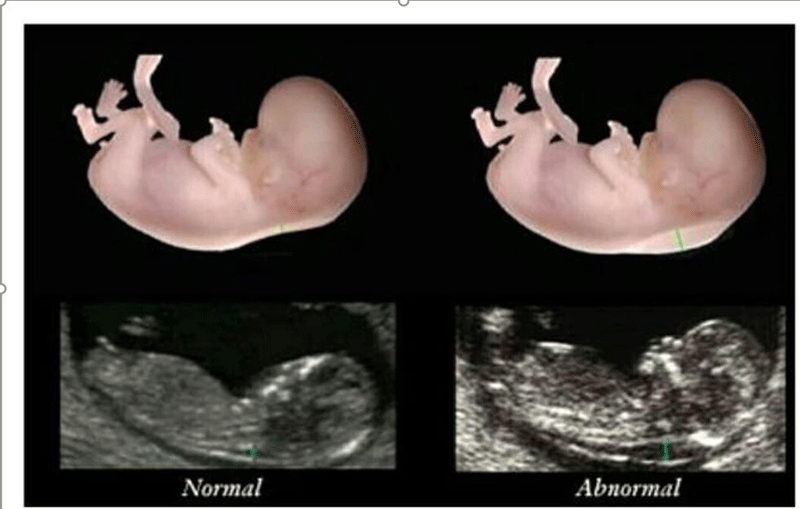

nt是胎儿颈后透明袋的简称,全称为(nuchal teanslucency),nt检查就是胎儿颈后透明带检查,检查胎儿颈后部皮下组织内液体积聚的厚度。

nt检查的主要作用就是获得nt值,通过nt值诊断胎儿是否正常,是否有染色体疾病和其他原因造成胎儿畸形,如果通过nt值提示胎儿有异常,在做四维彩超和唐氏筛查的时候将会重点关注。

nt检查正常值一般是在≤2.5mm,只要通过nt检查发现nt值在正常值范围内,就可不用担心了,nt检查属于一次检查。

2、如果没有测量误差,就是真正病理上的问题,就是胎儿染色体异常、胎儿大动脉畸形、胎儿静脉导管血流异常或者是淋巴系统排泄失常等原因,